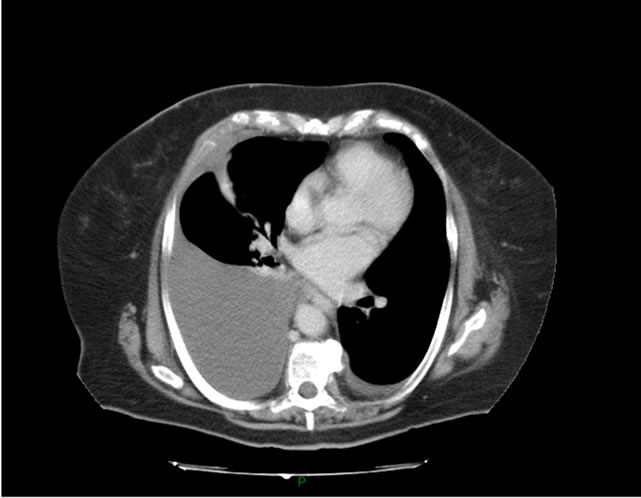

- Chụp X-quang: Phương pháp này giúp bác sĩ quan sát và đánh giá được các thành phần canxi trong vùng chậu.

- Siêu âm, chụp MRI CT vùng chậu.